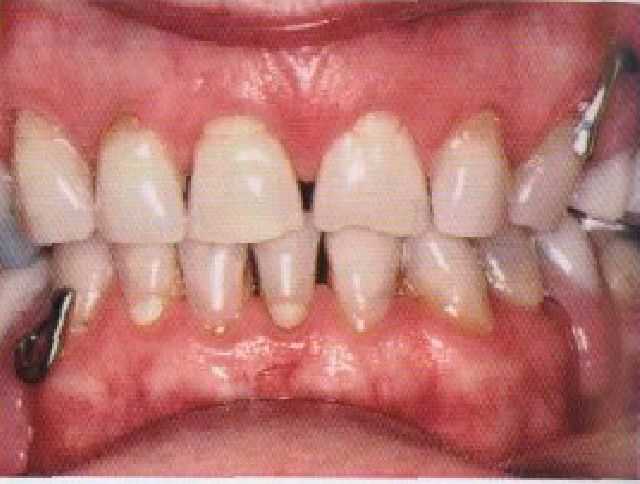

Рис. 3-7. Окклюзионные контакты частичных съемных протезов созданы таким образом, чтобы они совпадали с существующим межбугорковым соотношением и поддерживали его.

Это, безусловно, является хорошим приемом протезирования, который применяется в конструкции полного съемного протеза. Таким образом, если искусственные зубы должны улучшать функцию жевания, необходимо, чтобы они обеспечивали двусторонний и одновременный контакт между естественными и искусственными зубами, фиксируя при этом приемлемую окклюзионную высоту лица. Для многих пациентов это будет совпадать с существующим стабильным состоянием максимальных межбугорковых контактов (см. рис. 3-7),